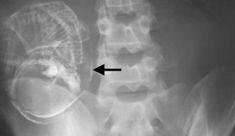

▼这类案例最有名的例子发生在1999年的印度,当时Sanju Bhagat出生时就腹部肿胀,但因为家境问题,父母从未带他就医。直到成年Sanju Bhagat自己去看诊时,才从肚子里拿出一个完整的人形胚胎…